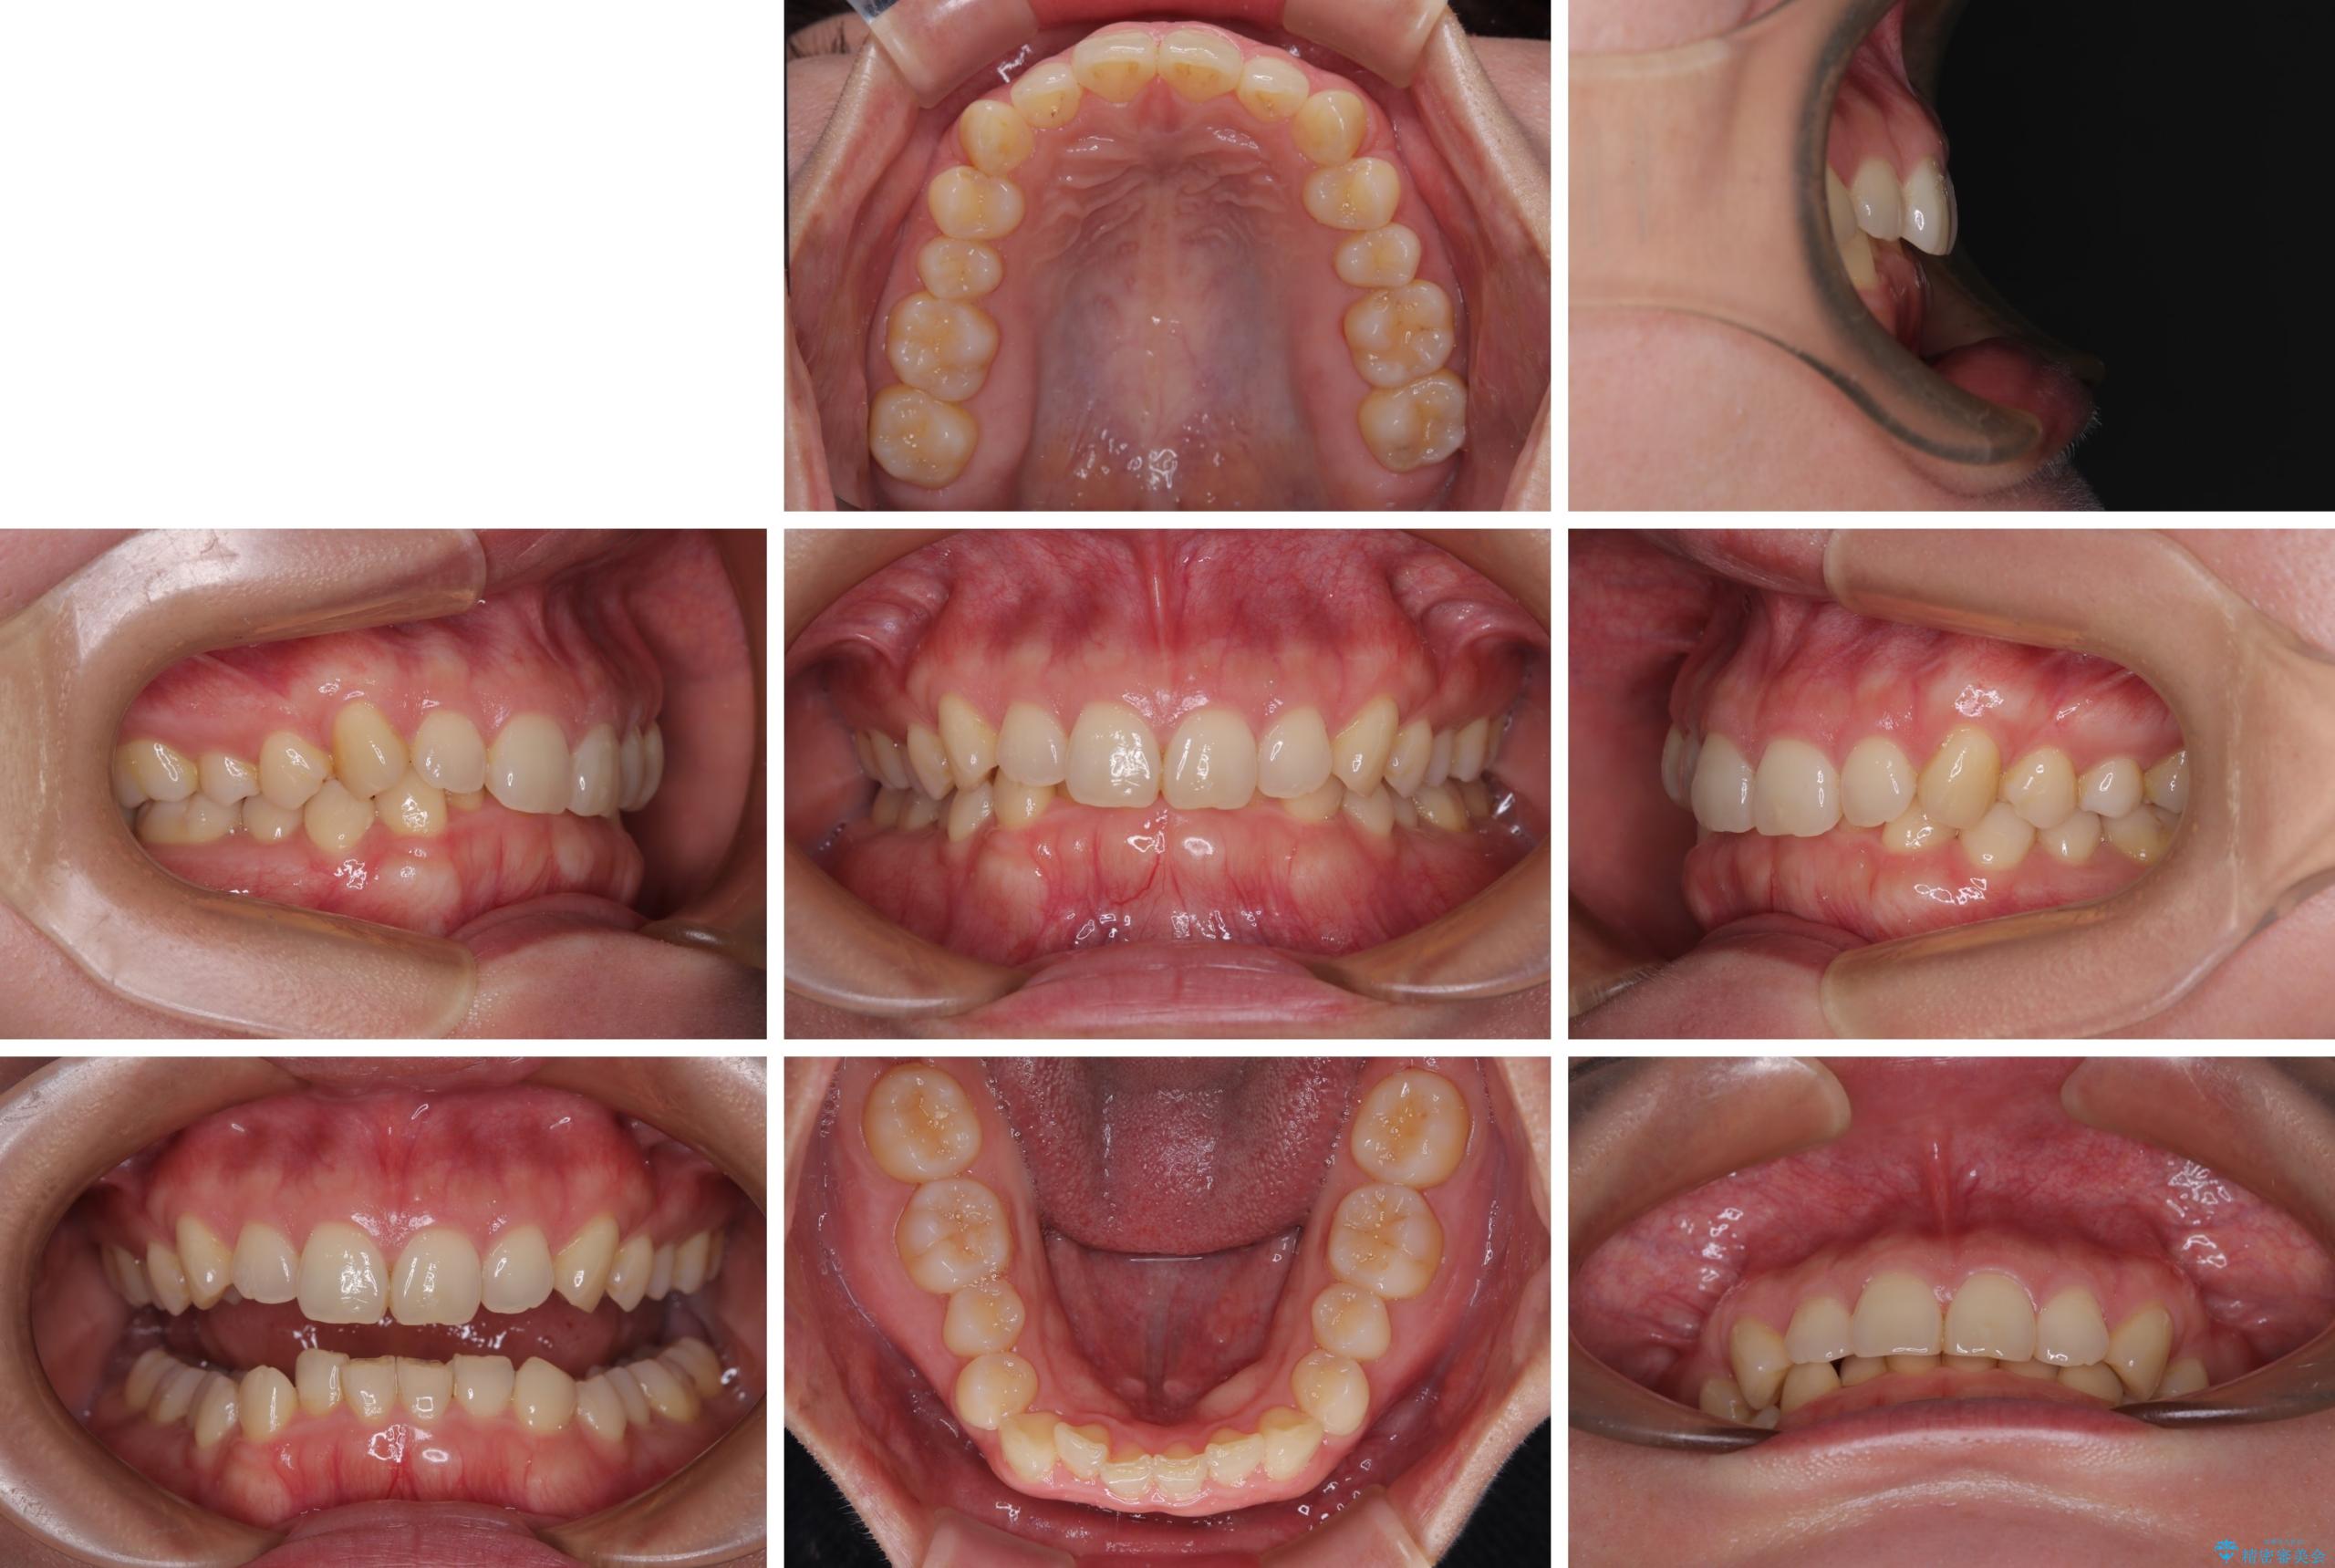

隠れた前歯が気になる ディープバイトのワイヤー矯正治療

- 下顎前歯が完全に隠れてしまっていることを気にして来院された患者様です。

下顎の臼歯が手前に傾斜していることで咬み合わせが深くなってしまい、下顎前歯が見えないほどに上顎前歯が覆い被さっている状態でした。

咬合力が強いことと、マウスピースを長時間装着する自信がないとのことで、ワイヤー装置にて矯正治療を行うこととしました。

下顎臼歯を起き上がらせるためにユーティリティーアーチを使用し、一気に深い咬み合わせを改善することができました。